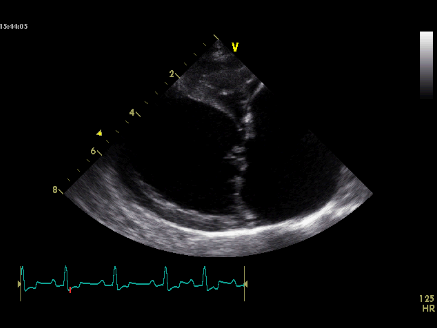

The owners are limited in what they can spend, and so they agree to an echo only. The echo confirms the suspicions of degenerative mitral valve disease (DMVD). Left atrial enlargement and left ventricular dilation is recorded. This puts Poppy in the American College of Veterinary Internal Medicine (ACVIM) stage B2 class.